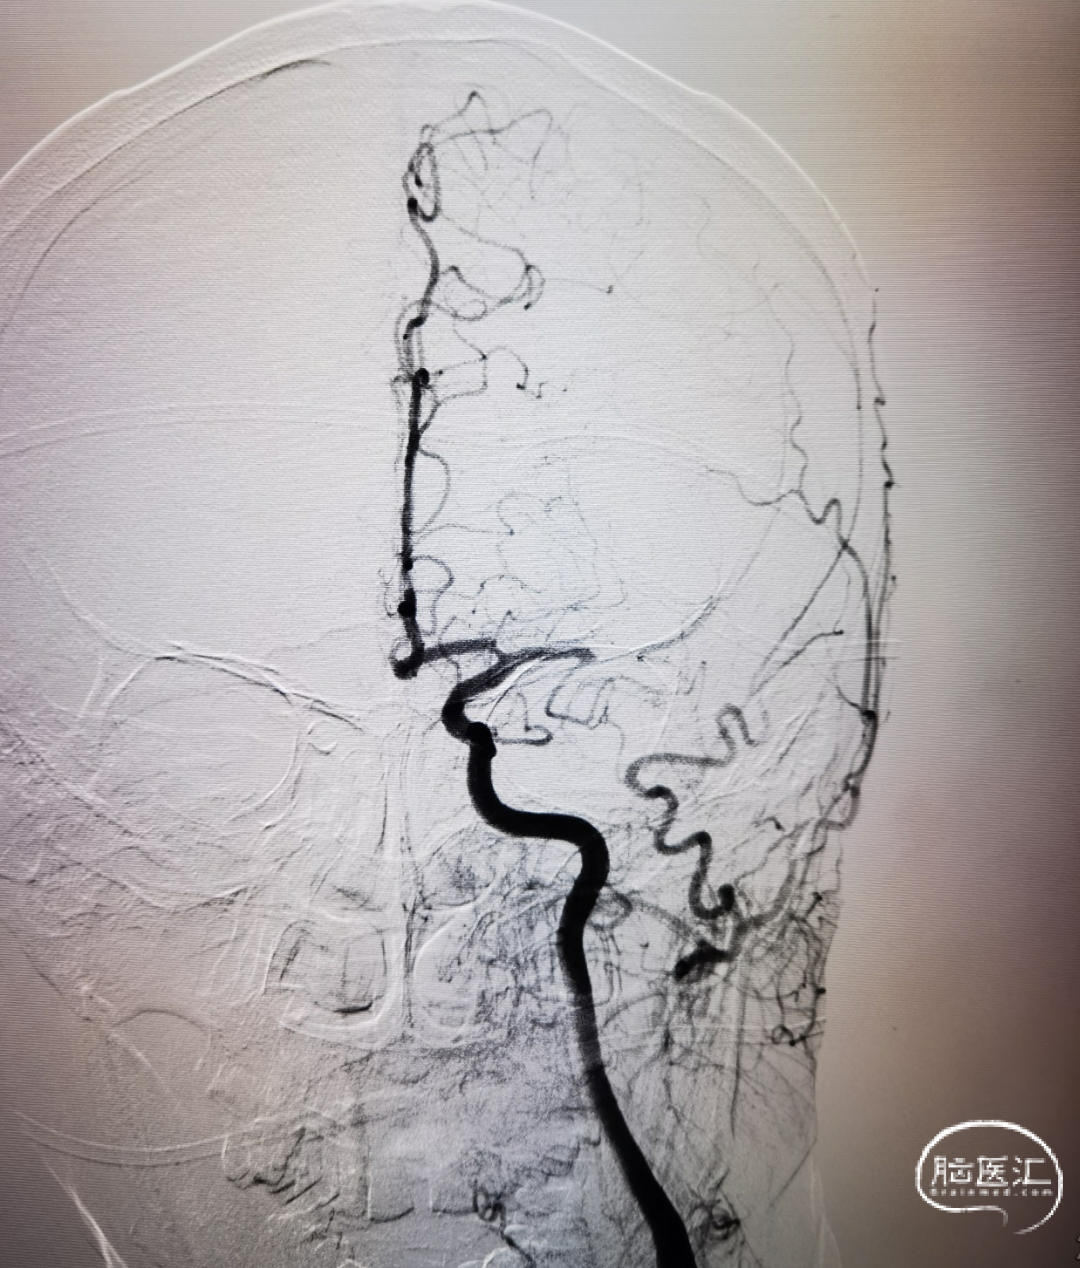

构建治疗通路,微导管穿过闭塞段后造影确认真腔,置入Syphonet®取栓支架,支架通体显影,提供良好的视觉反馈,全程可视化操作。

沿取栓支架的输送导丝送入SacSpeed®球囊扩张导管,将球囊置于狭窄段充盈球囊进行扩张。

完成扩张后。

球囊泄压后利用Syphonet®取栓支架的锚定效果让中间导管靠近闭塞段;撤出快交球囊后采用SWIM技术取栓;术后造影证实血管再通。

开通后血流再次闭塞,考虑球扩后夹层形成可能;补救性予以电解脱释放Solitarie支架后正侧位造影。